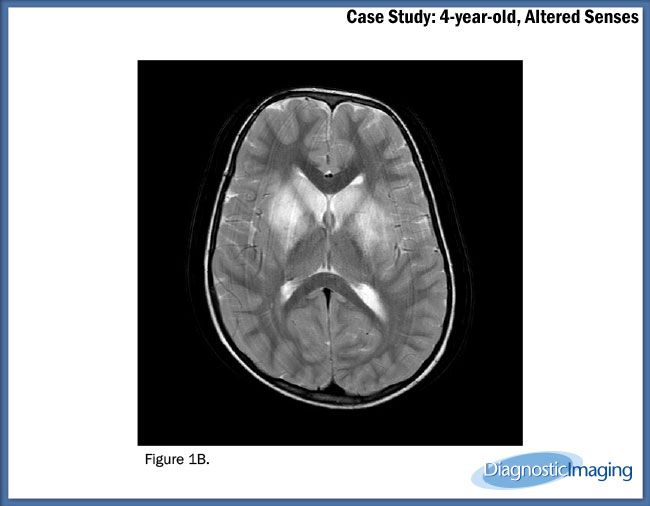

Case History: Four-year-old patient with complaints of altered sensorium.